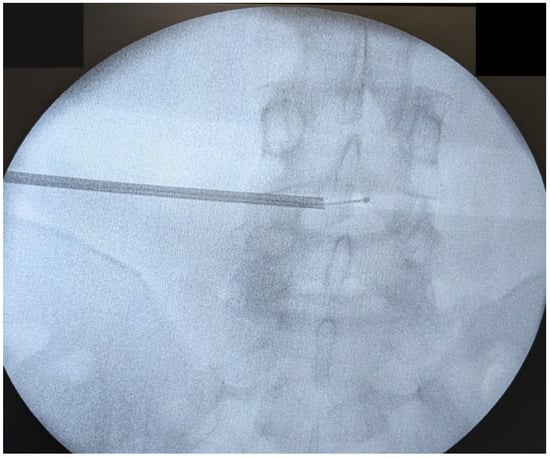

2.5. Surgical Procedure